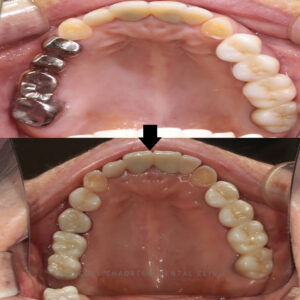

이 기간 동안 환자분은 브릿지를 잘라

사용한 작은 어금니의 심미적인

부분이 많이 아쉬우셨는지,

메탈로 된 예전 보철물 대신 이왕

치료하는 김에 앞쪽 작은 어금니도

예쁘게 만들고 싶다고 말씀하셨습니다.

다행히 작은 어금니의 내부 상태가

아주 양호해서 치아를 최대한

보존하면서 지르코니아 크라운으로

교체해드렸습니다.

지르코니아는 강도도 높고 색상도

자연치아와 유사하여 환자분께서도

만족도가 높으셨습니다.

약 한달 후, 최종 보철물을 제작하여

세마역임플란트를 마무리하였습니다.

최종 보철물은 마찬가지로

지르코니아로 제작되어 심미성과

기능성 모두 만족시킬 수 있도록 디자인하였습니다.